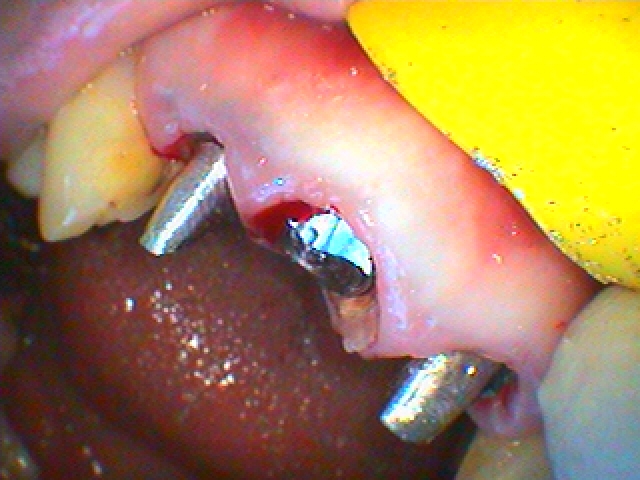

右上の1番部がコアごと脱離 歯に亀裂線も存在 破折と判断 審美領域のインプラント治療の臨床現場|お知らせ |広島市安佐南区の歯科医院 右上の1番部がコアごと脱離 歯に亀裂線も存在 破折と判断 審美領域のインプラント治療の臨床現場 トップ お知らせ・ブログ お知らせ 右上の1番部がコアごと脱離 歯に亀裂線も存在 破折と判断 審美領域のインプラント治療の臨床現場 右上の1番部がコアごと脱離 歯に亀裂線も存在 破折と判断 審美領域のインプラント治療の臨床現場 デンタルレントゲンになります 歯牙になります 唇側が破折していました 仮歯を入れていきました 抜歯即時インプラント埋入を行っていきました 仮歯を入れて終了となります デンタルレントゲンになります 3日後の状態になります Web診療予約 初めての方へ 選ばれ続ける理由 院内設備について 歯が痛いしみる一般歯科 歯がぐらぐらする歯周病 健康な歯を保ちたい予防歯科 子供の虫歯予防をしたい小児歯科 銀歯をセラミックに審美歯科 白い歯を目指しませんか?ホワイトニング 矯正専門医がいるので安心矯正歯科 抜けた歯を補いたいインプラント・入れ歯 医院案内 スタッフ紹介 メリィハウス歯科クリニックオフィシャルホームページ ラベンダー歯科クリニックオフィシャルホームページ お知らせ・ブログ ホーム 診療科目 一般歯科 歯周病治療 予防治療 小児歯科 審美治療 ホワイトニング 矯正歯科 入れ歯・インプラント マウスピース矯正 初めての方へ 院長・スタッフ 設備紹介 医院案内・アクセス メニューを閉じる